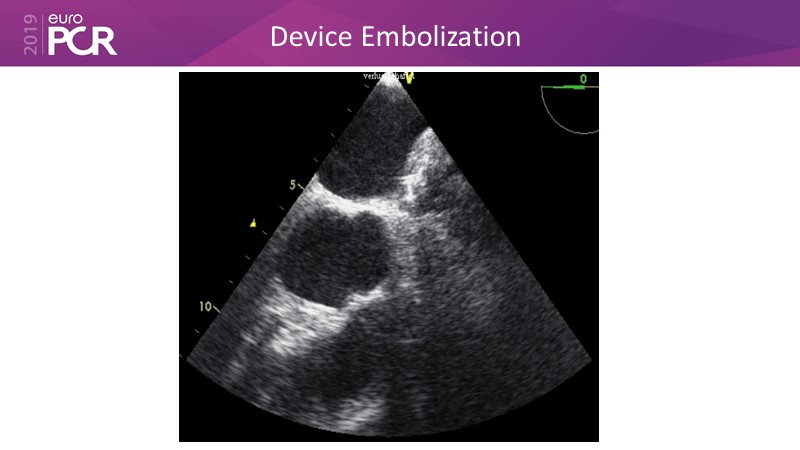

Optimising procedural outcome and safety

Previous Next